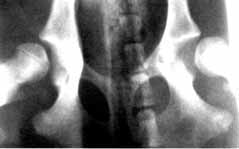

Gesunde Hüftgelenke (Baal "vom Gehrensee" - Aufnahme ohne Narkose)